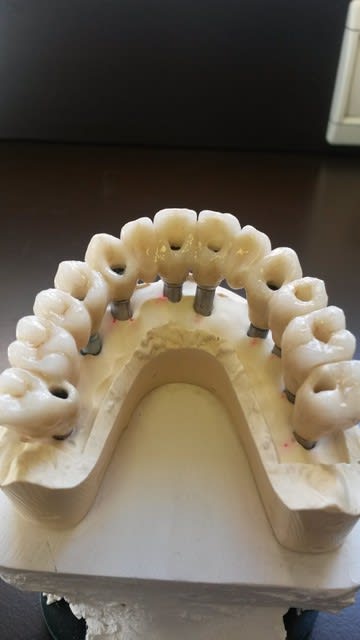

bonjour, pour des implantos exclusifs c'est surement fréquent, mais pour un omnipraticien comme moi, c'est pas tout les jours ! j'étais content en fin de traitement.

joli, 10 implants intelligemment répartis, même si un de perdu.